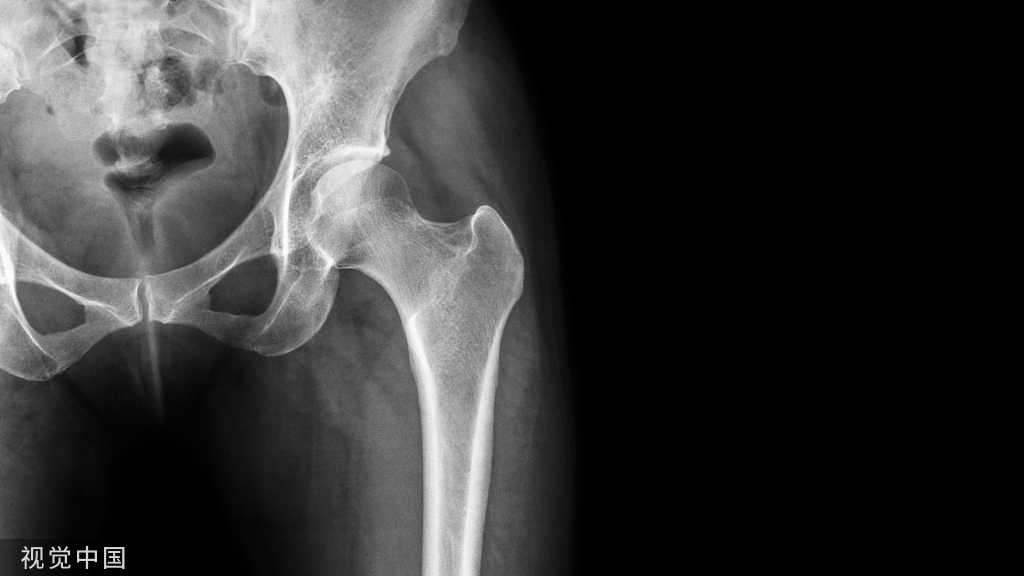

09股骨颈应力性骨折

股骨颈应力性骨折与骨折不愈合密切相关,早期诊断及积极干预至关重要。股骨颈营应力性骨折多见于运动员长跑时反复局部负重或芭蕾舞演员反复大跳或开髋单足过多旋转造成。